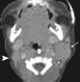

Sternocleidomastoid muscle hypertrophy

Spasmodic torticollis is an extremely painful chronic neurological movement disorder causing the neck to involuntarily turn to the left, right, upwards, and/or downwards. The condition is also referred to as "cervical dystonia". [Source: Wikipedia ]